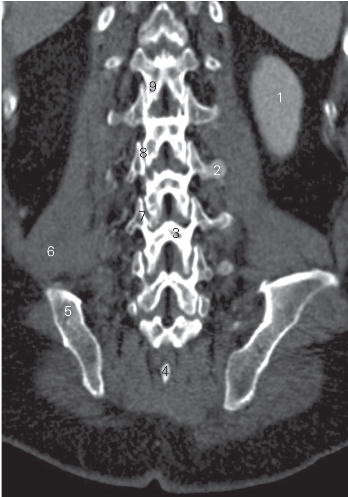

图3-8 经腰椎椎弓板的冠状曲面重建CT图像(骨窗)

1 左肾 left kidney 2 横突 transverse process

3 椎弓板 lamina of vertebral body 4 棘突 spinous process

5 髂骨 ilium 6 腰大肌 psoas major

7 上关节突 superior articular process 8 关节突关节 zygapophysial joint

9 下关节突 inferior articular process